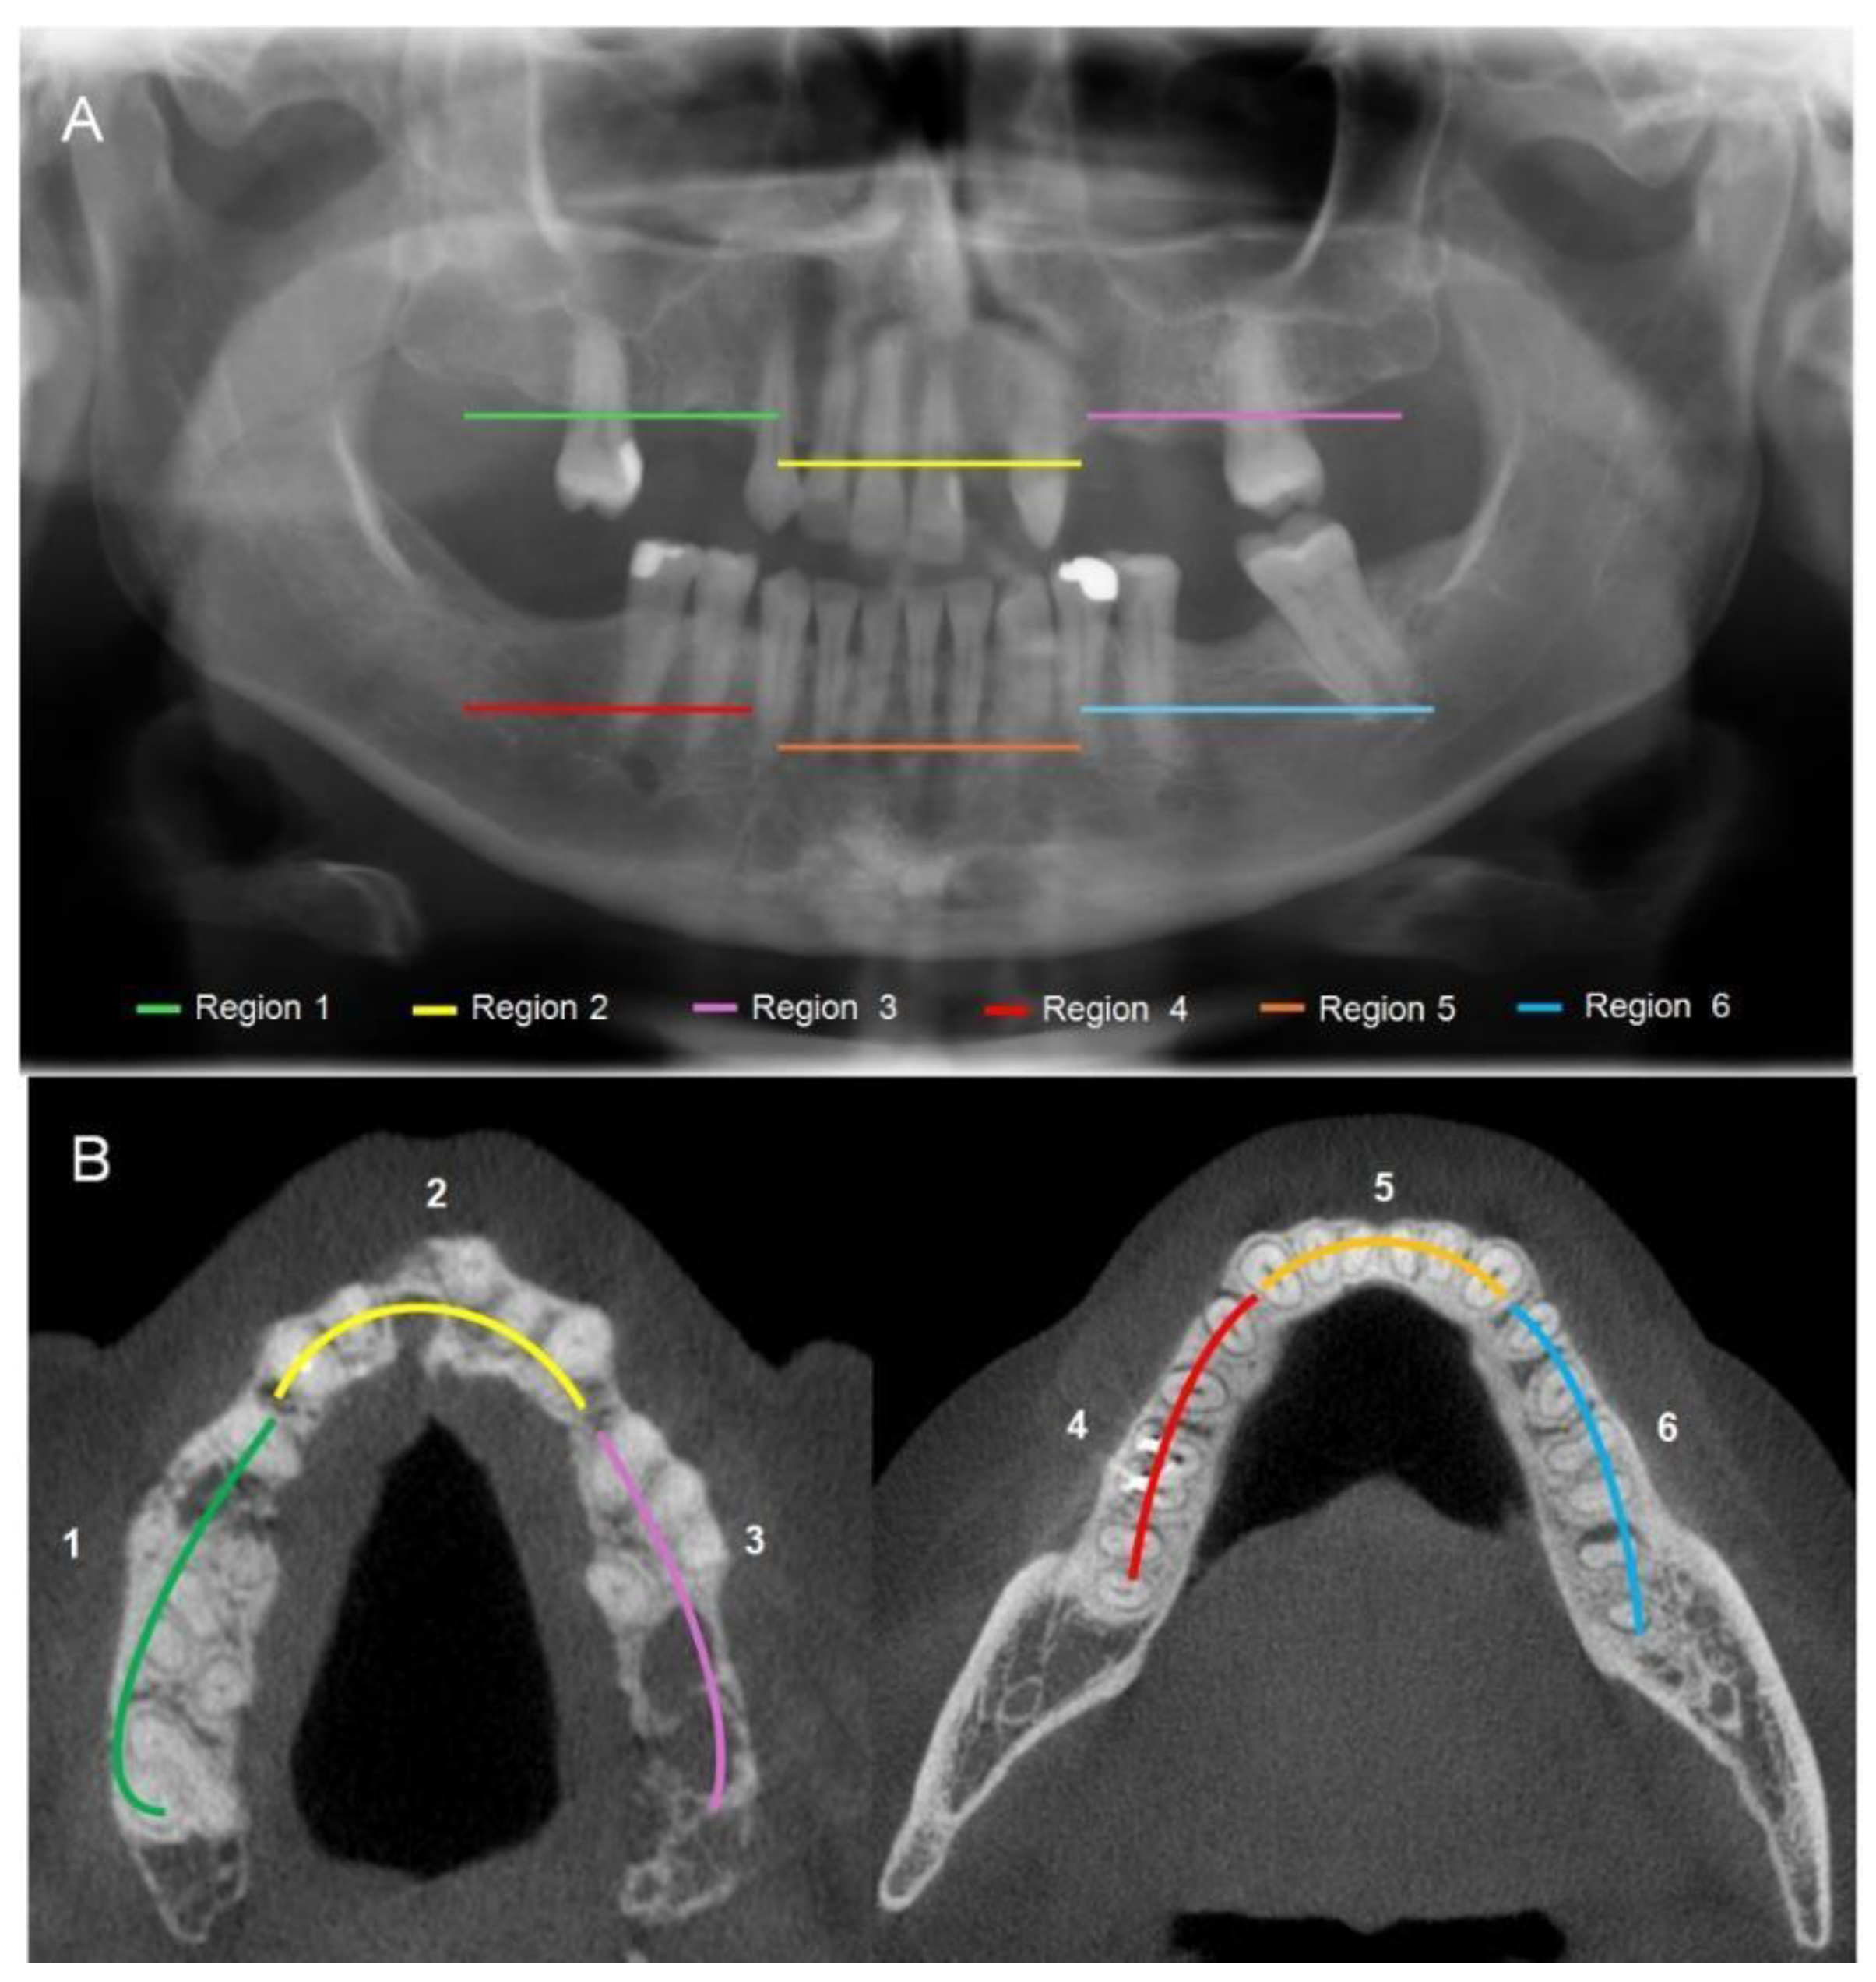

3.3.1. Bone Features on Panoramic Radiography (PAN)

3.3.2. Bone Features on Cone Beam Computerized Tomography (CBCT)

3.3.4. CRIm Distribution According to Anatomical Region